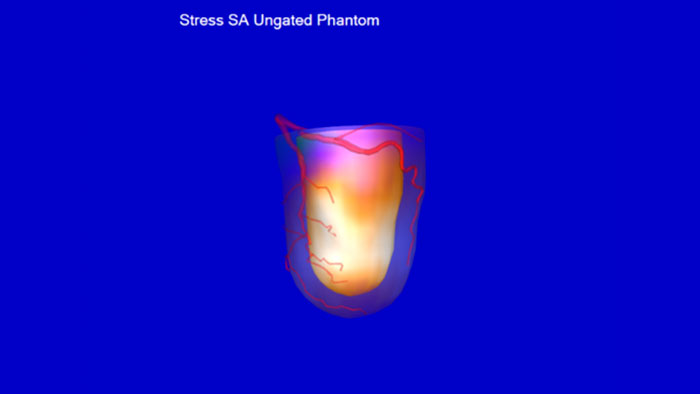

- Emory Cardiac Toolbox (ECTb) HeartFusion

-

Emory Cardiac Toolbox (ECTb) HeartFusion*

Evaluate fused coronary anatomy

Emory Cardiac Toolbox (ECTb) HeartFusion offers fusion of a patient’s coronary tree from cardiac CT angiography with MI perfusion images.

Benefits

- Helps correlate stenosis with perfusion defects and identify muscle mass at risk.

*Emory Cardiac Toolbox, ECTb, HeartFusion, and SyncTool are registered trademarks of Emory University.